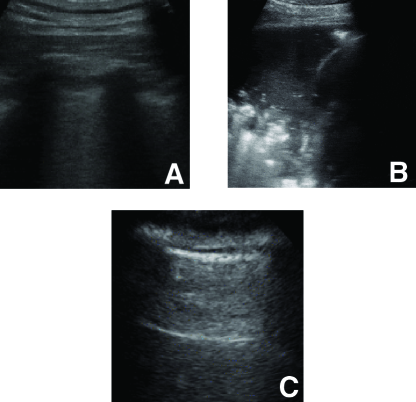

Figure 1: Example lung ultrasound images of the database. A: A typical COVID-19 infected lung, showing small subpleural consolidation and pleural irregularities. B: A pneumonia infected lung, with dynamic air bronchograms surrounded by alveolar consolidation. C: Healthy lung. The lung is normally aerated with horizontal A-lines. All images were scraped from publicly available sources.

Ultrasound can evidence pleural and interstitial thickening, subpleural consolidation and other physiological phenomena linked to changes in lung structure when the infection is in early stages [19]. Studies report abnormalities in bilateral B-lines (hydroaeric comet-tail artifacts arising from the pleural line), as well as identifiable lesions in the bilateral lower lobes as the main characteristics to enable COVID-19 detection [47, 48]. In Figure 1 an example of B-lines visible in the US image of a COVID-19 patient is shown. In a review, [46] observed great agreement between ultrasound and CT when monitoring COVID-19 patients (especially between B-lines in ultrasound and GGOs in CT [49]) and concluded a high potential for ultrasound in evaluating early lung patients, especially to guide subsequent testing in triage situations. Others reported concordance between US and chest recordings in 7/8 monitored adolescents with COVID-19, while the last patient had a normal radiography despite irregular US [22]. For a review on the timeline of US findings in relation to CT see [50].

Since the 64 videos were taken from various sources, the format and illumination differ significantly. In order to generate a diverse and still sufficiently large data set, images were selected from the videos with a frame rate of 3Hz and a maximum of 30 frames per video. This resulted in an average of 17±6plus-or-minus6\pm 6 frames per video and a total of 1103 images (654 COVID-19, 277 bacterial pneumonia, 172 healthy). To homogenize the dataset, we cropped the images with a quadratic window excluding measure bars and texts visible on the sides or top of the videos. Five videos were manually processed with Adobe After Effect in order to remove measure scales and other artifacts that were overlaying the US recording. Examples of the cropped images are shown in Figure 1. We are however aware that the heterogeneity of the data is still problematic, and we are constantly searching for more data to prevent the model from over fitting on the specific properties of the available recordings.